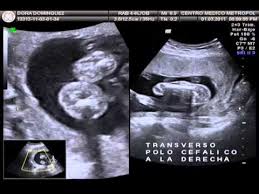

Cómo saber si es niño o niña síntomas. Otra forma que es poco común primero. Una ecografía siempre será el método más fiable y aún así el doctor también se puede confundir según la postura. La gestación y el embarazo sin duda es uno de los acontecimientos más emocionantes e importantes para una pareja.